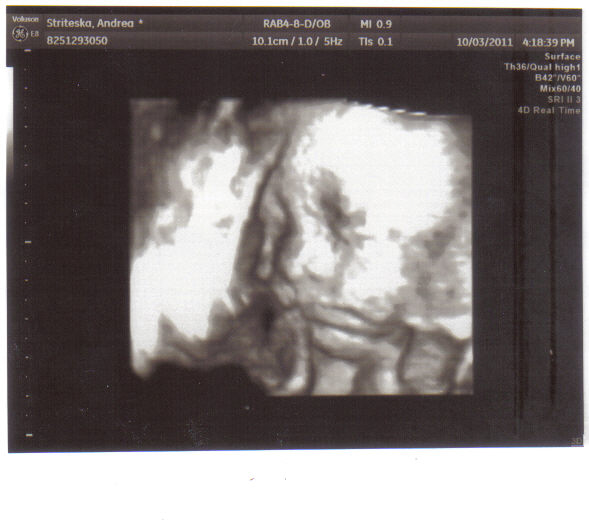

| Souvisí s: | období 185 dnů těhotenství (Zobrazit galerii období) |